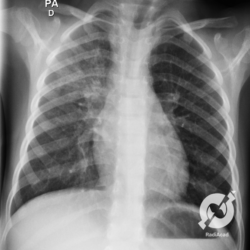

Os agentes etiológicos infecciosos são variados (bactérias, vírus, fungos, parasitas…), mas o que ocorre nos pulmões durante uma infecção por qualquer tipo de agente é a substituição do ar alveolar por secreção (pus, muco, eventualmente sangue ou necrose…) e com isso a manifestação radiográfica vai ser a mesma já que todas estas secreções apresentam a mesma densidade radiográfica: partes moles.

E o nome dado a esta alteração radiográfica que corresponde à substituição do ar alveolar por líquido é a consolidação alveolar.

Uma consolidação alveolar é, por definição, uma opacidade (imagem densa, branquinha) homogênea ou às vezes heterogênea (pela presença de calcificações ou cavidades), de limites mal definidos, exceto quando toca a pleura da parede ou das cissuras pulmonares. É um termo usado tanto em radiografia, como em tomografia computadorizada. Na tomografia, um outro termo é usado: vidro fosco, que é uma opacidade (branquinha mas não tanto como a consolidação), que borra o pulmão mas deixa ver os vasos de permeio (igual bigode de adolescente: dá pra ver todo o fundo).

Nós vamos mostrar aqui um pequeno apanhado de pneumonias de variados agentes, em diversos segmentos e lobos pulmonares, com extensões variadas. O objetivo é identificar o padrão radiológico de consolidação alveolar e não determinar o agente infeccioso, isso vai ser assunto para mais adiante. Aliás já antecipo que é fundamental saber localizar a lesão, porque alguns destes bichos gostam de determinados segmentos, alguns tumores também têm as suas preferências, então localização é fundamental. Se localização não fosse importante, um apartamento na beira do mar sairia o mesmo preço de um apartamento de frente pra BR-101, concordam?

Seguem alguns dos nossos casos de pneumonia para vocês treinarem os olhos e não se apavorarem nos plantões.